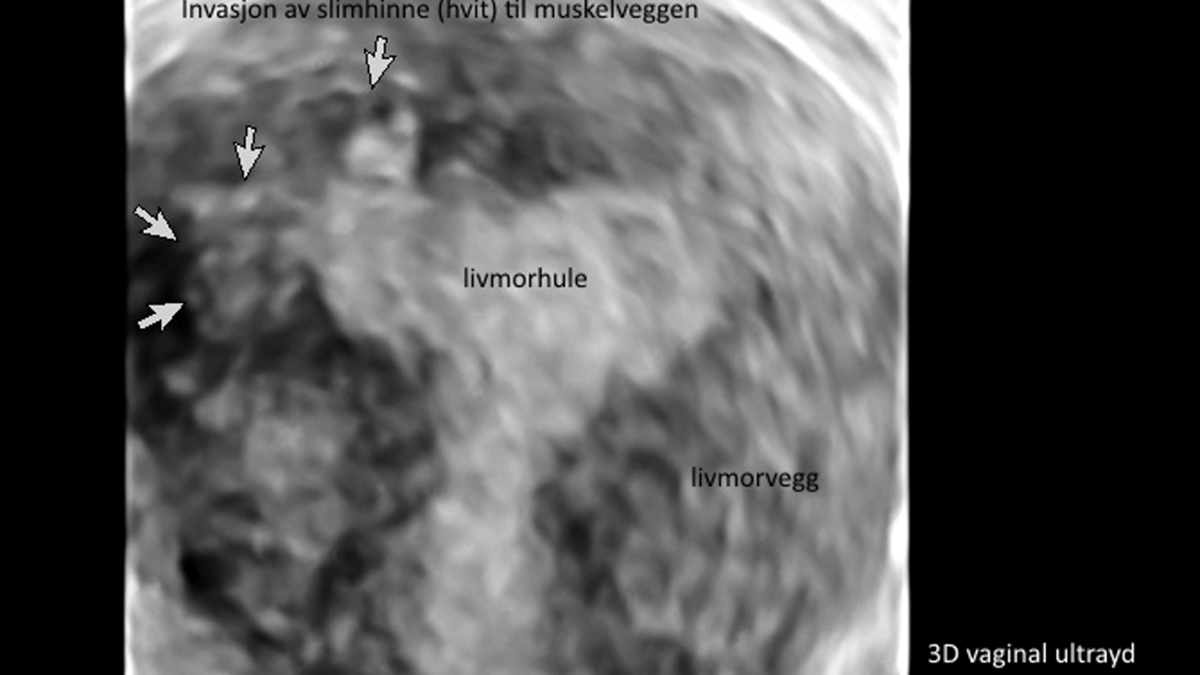

Ved en indvendig ultralydsundersøgelse (vaginal ultralyd) kan man opdage ca. 87% af alle tilfælde. Gynækologen mistænker adenomyose, hvis livmoderen er sfærisk/kugleformet, forstørret eller virker asymmetrisk og med vægge, som er forskellige af tykkelse. Nogle gange vil man kunne visualisere små blodfyldte cyster i muskelvæggen.